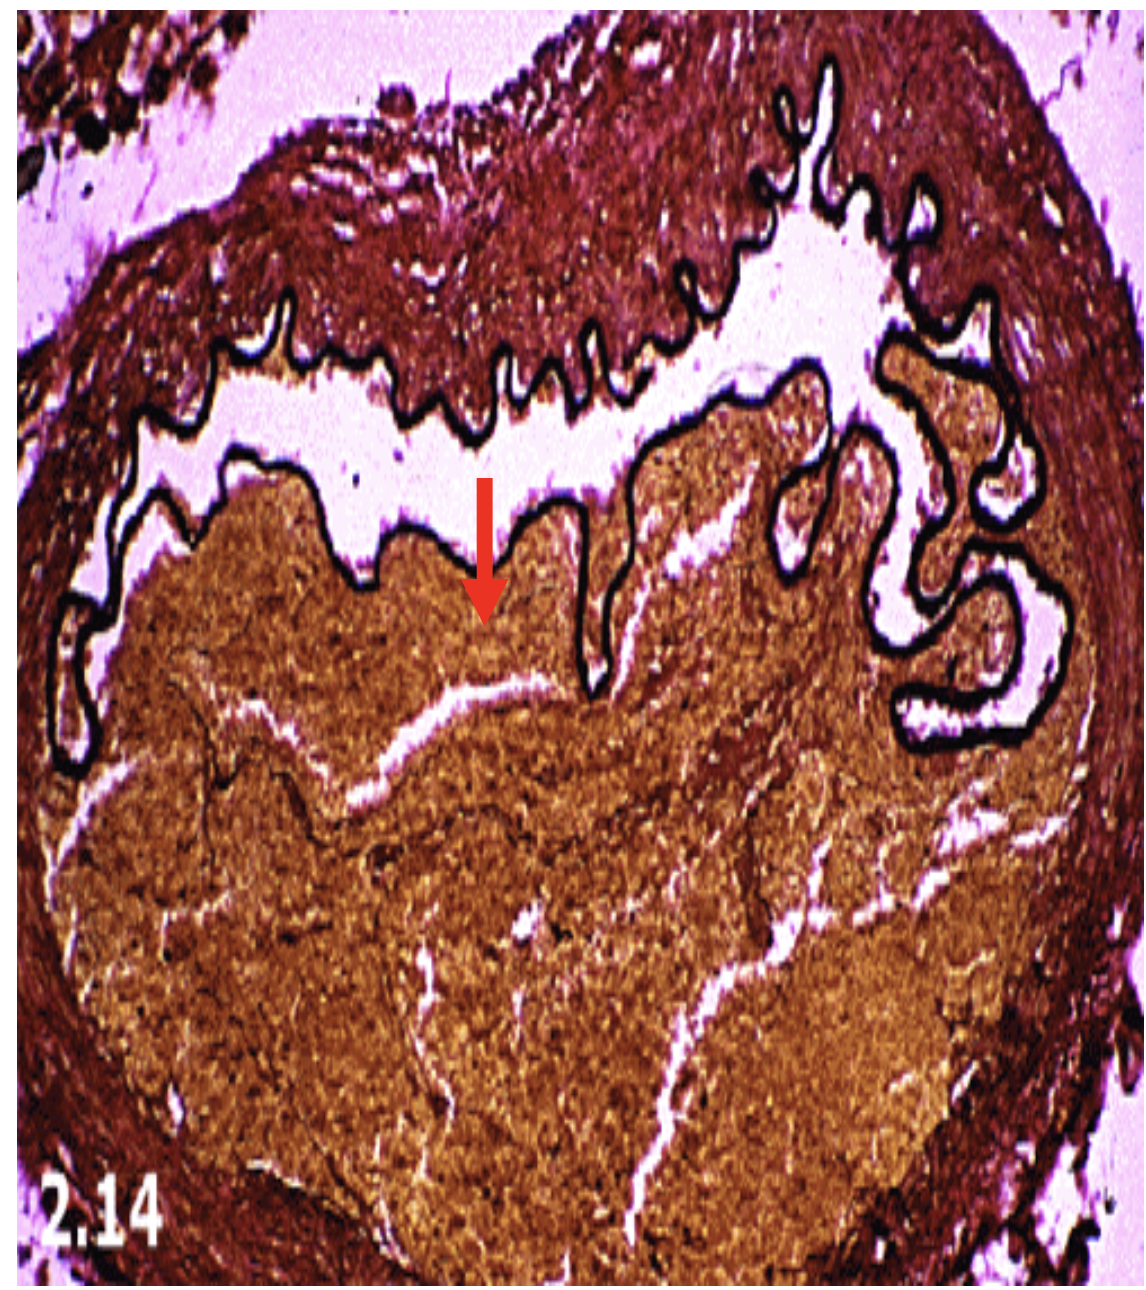

AVMs

Located in cortex

Composed of both large arteries (open arrow) and veins (solid arrow) without intervening capillaries.

Between vessels there is gliotic nonfunctional hemosiderin stained tissue (circle).